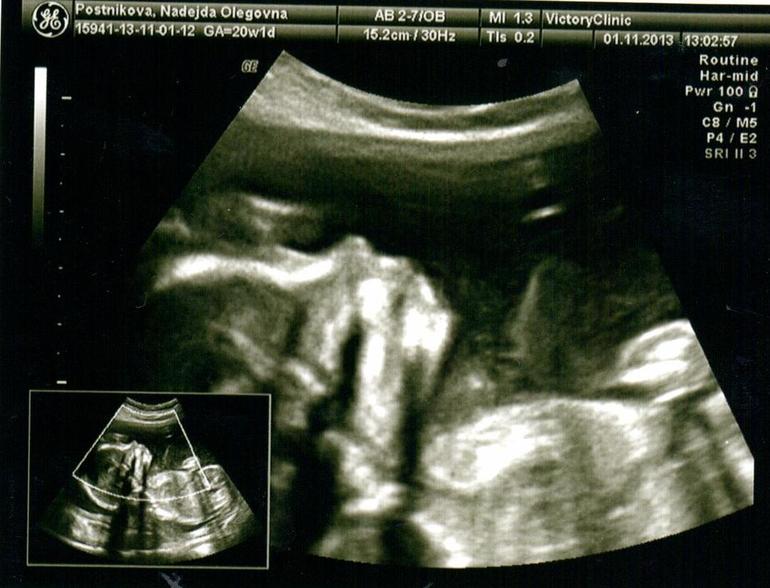

Сегодня я по особенному счастливая и наш с пузиком экватор - не единственная тому причина, причин у нас много - сегодня мы были на УЗИ (подглядывали за нашим сокровищем), до сих пор эмоции переполняют… :) У нас все хорошо, развиваемся по сроку, уже довольно-таки большие - 330 грамм )) Мы узнали пол, я аж прослезилась от счастья ))) Муж тоже очень рад, от чего я счастливее вдвойне )))

Собственно говоря, вот и мы:

Себе на память результаты УЗИ:

Нам сказали, что головка у нас долихоцефалической формы (такая обычно у детишек после естественных родов, т.е. чуть вытянутая, но сказали, что до родов она еще изменится) и еще утолщенная плацента, вот это меня не очень порадовало :( На ЗППП сдавала, все чисто, анемия у меня совсем слабая, все другие причины тоже ко мне не относятся, так что повлиять могла на это либо простуда, перенесенная в первом триместре, либо мой офисный режим работы (отсутствие кислорода), теперь просто уверена как никогда, что морской воздух мне пойдет на пользу )))